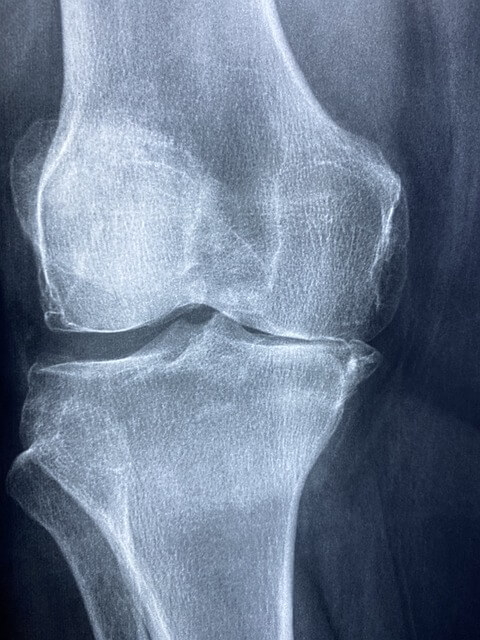

무릎 관절염으로 인한 심한 통증과 변형이 있는 경우, 근위경골절골술이 적합할 수 있습니다. 병원에 가면 의사는 검사, X-ray 및 MRI를 통해 뼈의 상태를 평가하고 수술이 적합한지 여부를 결정하게 됩니다.

근위경골절골술은 무릎 안쪽 뼈인 근위경골이 골절되었을 때 뼈를 다시 정렬하고 고정하기 위한 수술입니다.

주로 무릎 관절염으로 인한 통증과 변형을 완화하기 위해 시행됩니다.

※저의 경우 연골이 완전히 마모되어서 오른쪽 무릎이 한쪽으로 기울어지며 다리에 변형이 오고, 다리 길이가 달라져서 다리를 절어서 하게 되었습니다.